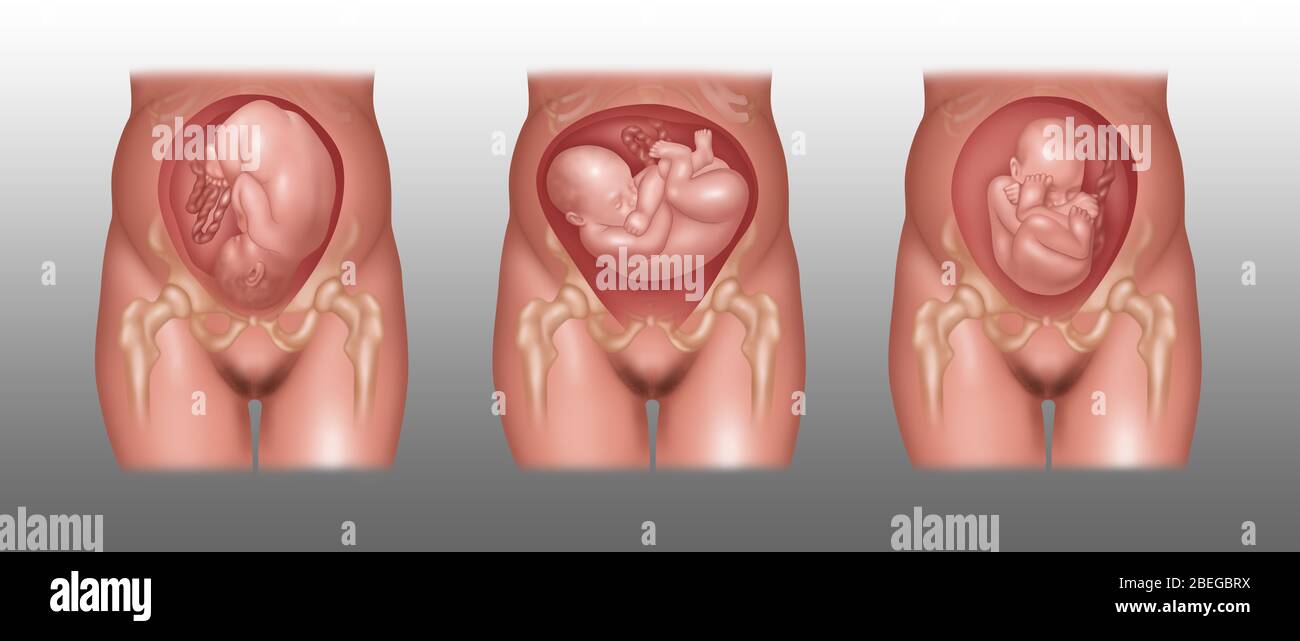

Fetus Positions in Uterus, Illustration Stock Photohttps://www.alamy.com/image-license-details/?v=1https://www.alamy.com/fetus-positions-in-uterus-illustration-image353173031.html

Fetus Positions in Uterus, Illustration Stock Photohttps://www.alamy.com/image-license-details/?v=1https://www.alamy.com/fetus-positions-in-uterus-illustration-image353173031.htmlRF2BEGBPF–Fetus Positions in Uterus, Illustration

Fetus Positions in Uterus, Illustration Stock Photohttps://www.alamy.com/image-license-details/?v=1https://www.alamy.com/fetus-positions-in-uterus-illustration-image353173074.html

Fetus Positions in Uterus, Illustration Stock Photohttps://www.alamy.com/image-license-details/?v=1https://www.alamy.com/fetus-positions-in-uterus-illustration-image353173074.htmlRF2BEGBT2–Fetus Positions in Uterus, Illustration